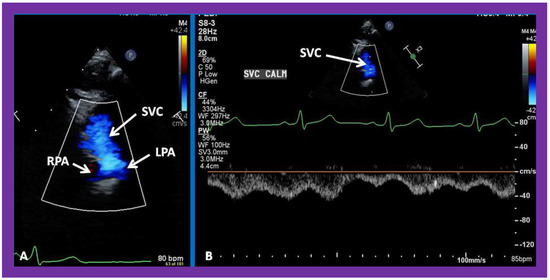

5.3. Echocardiographic Evaluation Following Bidirectional Glenn

Following bidirectional Glenn, the LV size is likely to decrease (normalize) and LV should maintain normal systolic function. This is because of decreased LV volume overload following bidirectional Glenn and the removal of aorto–pulmonary shunt. The 2D imaging of the bidirectional Glenn is difficult to accomplish, but color flow imaging (Figure 25A, Figure 26B, and Figure 27B) from a suprasternal notch or high parasternal views will help image the bidirectional Glenn. Low pulsed Doppler velocity across the superior vena cava (SVC)–PA junction (Figure 25B and Figure 26C) would indicate no obstruction. Turbulent and high velocity Doppler flow suggests the obstruction of the bidirectional Glenn shunt. The size of the branch PAs may be assessed with a combination of 2D and color flow imaging (Figure 26, Figure 27 and Figure 28).

Figure 25. Selected video frames from suprasternal notch view demonstrating bidirectional Glenn shunt; the superior vena cava (SVC) is shown emptying into the right (RPA) and left (LPA) pulmonary arteries by color flow imaging (A). Low Doppler flow velocity across the shunt (B) indicates unobstructed Glenn.

Figure 26. (A,B) Selected video frames from suprasternal notch view demonstrating bidirectional Glenn shunt. In (A), the right (RPA) and left (LPA) pulmonary arteries are shown by 2D. The superior vena cava (SVC) was not clearly seen. In (B), the SVC is shown emptying into the RPA by color Doppler (B). The LPA did not show color flow because it was in a different plane of imaging than RPA, but is seen by 2D (B). (C) Low Doppler flow velocity across the Glenn shunt indicates unobstructed flow.

Figure 27. Selected video frames from suprasternal notch view demonstrating bidirectional Glenn shunt; the superior vena cava (SVC) is shown emptying into the right (RPA) and left (LPA) pulmonary arteries by two dimensional (A) and color flow imaging (B). Both RPA and LPA are seen with color in contrast to that seen in Figure 26, probably related to both pulmonary arteries are in a similar echo plane.